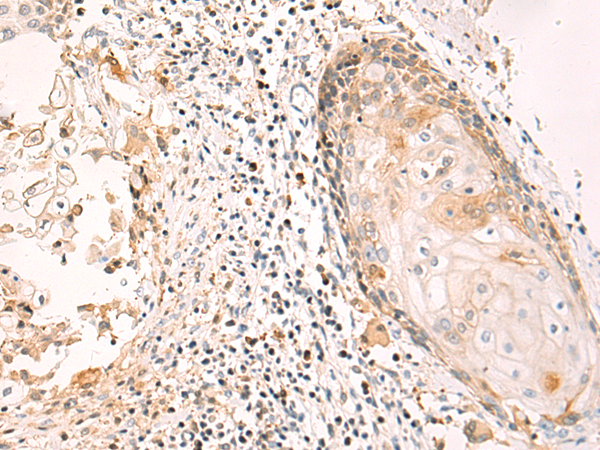

ELISA, IHC |

IHC positive control: |

Human esophagus cancer and Human tonsil |

IHC Recommend dilution: |

50-100 |